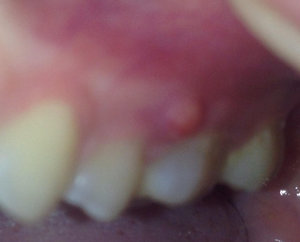

Два года назад мне выдрали зуб, было все хорошо два года. Запломбировали зуб поставили штифт, после возникла какая-то шишка. Пошла к хирургу, сказали киста, вырезали дней шесть назад, шишка стала еще больше, когда трогаешь чувствуешь, что она там есть, сегодня сходила к хирургу, сказала эту шишку постоянно массировать, и антибиотики прописали. Как говорит хирург, там опять образовалась пустота в этом же месте и по какой-то причине она не зарастает. Если она не пройдет, сказали пошлют на биопсию.

Мможет ли, что вот этот зуб со штифтом дает такую реакцию? Температура 37 - 37.3, у хирурга дошло уже дело до биопсии. Подскажите, может, и не надо эту шишку трогать, это же воспалительный процесс какой-то?